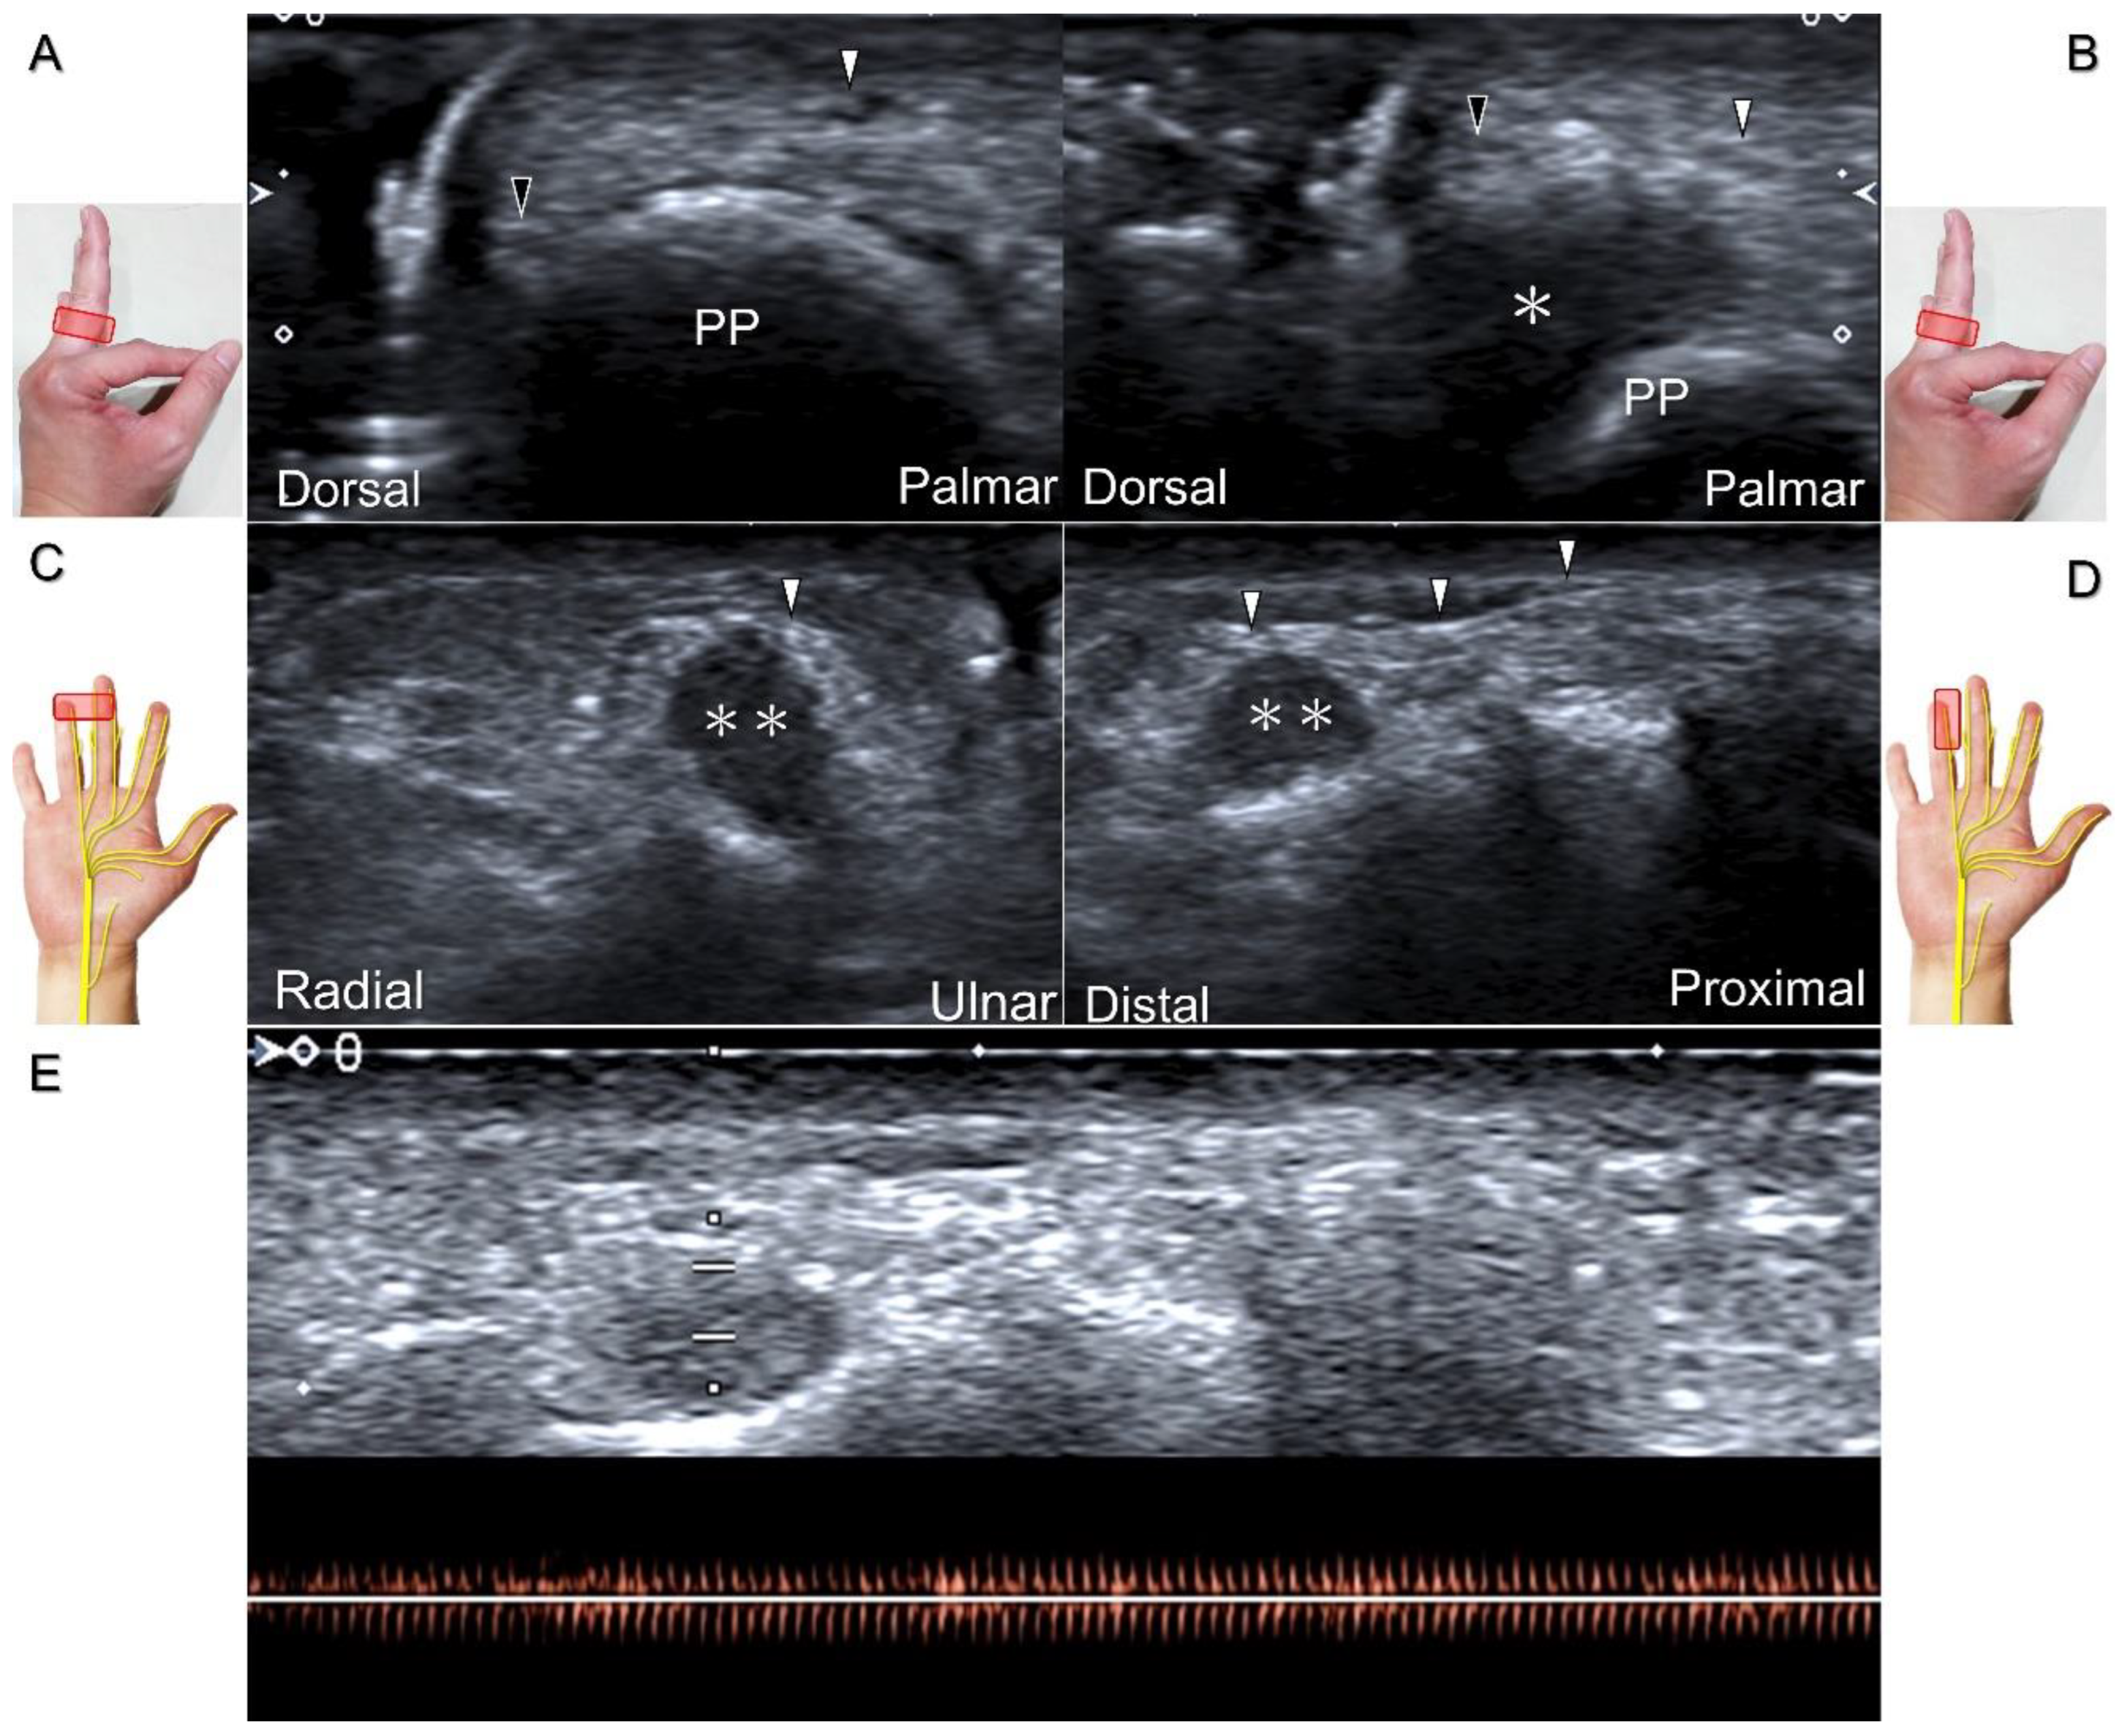

Direct injury of the palmar common digital nerve can occur due to various reasons such as trauma, contusion, or iatrogenically during tendon injection. Nerve entrapment caused by space-occupying lesions such as fractures, ganglia (Figure 29A–C), annular ligament tears (Figure 29D), tenosynovitis, foreign bodies, fibroma (Figure 30A,B), or hemangioma (Figure 30C–E) is also likely.

Figure 30. In comparison to the healthy side (A), short-axis imaging (B) shows irritation of both the palmar and dorsal proper digital nerves due to a fibroma (asterisk). Short-axis (C) and long-axis (D) imaging demonstrates irritation of the palmar proper digital nerve due to a hemangioma. Spectral Doppler mode (E) confirms the hemangioma. White arrowhead: palmar proper digital nerve; black arrowhead: dorsal proper digital nerve; double asterisk: hemangioma; PP: proximal phalanx.